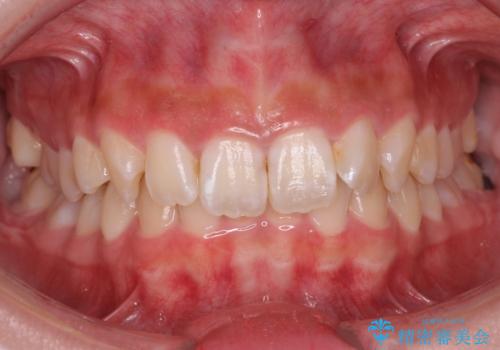

- 前歯のがたつきと左下の歯がうまっているとのことで、矯正治療を希望されました。

埋まっている奥歯を並べることで、その後ろの倒れ込んだ歯を整直させることができました。

引っ張り出すことはマウスピース矯正では難しい為、埋まっている歯を並べるスペース確保と、引っ張り出すのに、ワイヤーを用いた部分矯正を行なっています。

上の歯はマウスピース矯正で、奥歯を後ろに下げて、左のかみ合わせのズレを直しています。

上下とも非抜歯で並べています。

また、左上の変色した前歯はセラミックでやりかえを行なっています。

埋まっていた歯をしっかり引っ張り出すことができ、また、前歯の見た目も非常に良くなりました。

ワイヤー矯正を奥歯の部分的に行なっただけで、治療の大半をマウスピース矯正で行うことができ、非常に喜んでいただきました。